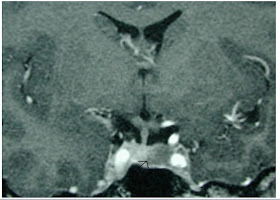

Pituitary adenoma (arrow shows dark shadowed area to the right)

- Radiology of the Pituitary -

Endotext Chapter 4 : Neuroendocrinology, Hypothalamus and Pituitary

http://www.endotext.org/neuroendo/neuroendo4/neuroendoframe4.htm